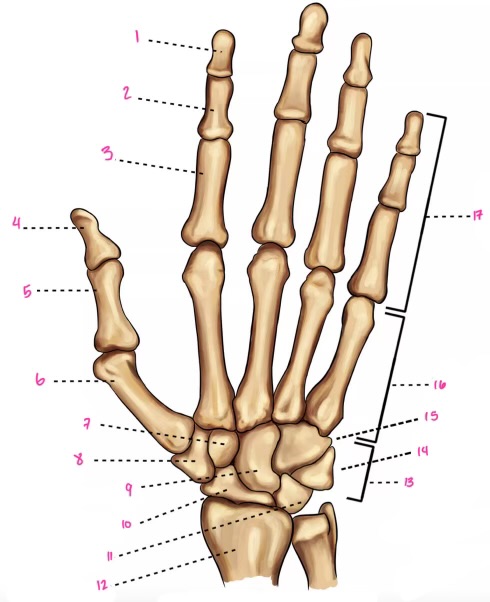

1

1

Hamate

2

New cards

2

Capitate

3

New cards

3

pisiform

4

New cards

9

Trapezoid

5

New cards

10

Trapezium

6

New cards

11

Scaphoid

7

New cards

14

Lunate

8

New cards

15

Triquetrum

9

New cards

16

Pisiform

10

New cards

17

Capitate

11

New cards

18

Hamate

1

Distal interphalangeal

13

New cards

2

Proximal Interphalangeal

14

New cards

3

Metacarpophalangeal

15

New cards

4

Intercapals

16

New cards

5

Distal radioulnar

17

New cards

6

Radiocarpal

18

New cards

7

Carpometacarpals

19

New cards

8

Metacarpophalangeal

20

New cards

9

Interphalangeal

7

Trapezoid

22

New cards

8

Trapzium

23

New cards

9

Capitate

24

New cards

10

Scaphoid

25

New cards

11

Lunate

26

New cards

13

Carpus

27

New cards

14

Triquetrul

28

New cards

15

Hamate

29

New cards

16

Metacarpus

30

New cards

17

Phalanxes